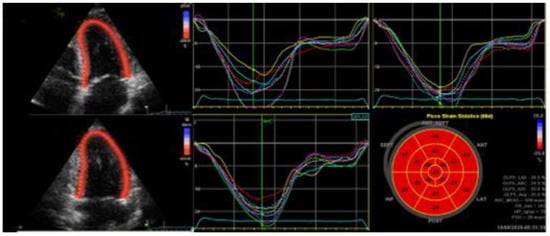

2.1.1. HFrEF